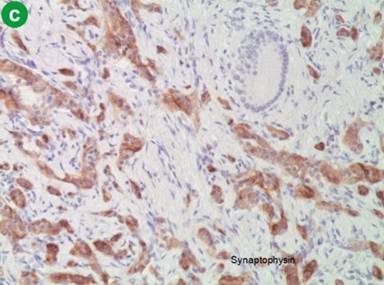

The patient presented a week later with worsening of upper abdominal pain. He had elevated transaminases, alkaline phosphatase, amylase and lipase times 2-4 the upper limit of normal, but normal serum bilirubin with fractions. A CT scan of abdomen and pelvis revealed an interval placement of a common bile duct stent with decompression of biliary system and a persistent prominence of pancreatic head. A magnetic resonance cholangiopancreatography showed a focal 80% narrowing of common bile duct with the presence of a stricture. The obstructive lesion was felt to be rather intraluminal or intramural than extrinsic in nature. The patient underwent a partial pancreaticoduodenectomy with gastrojejunostomy tube insertion. A white well-circumscribed, firm nodular mass measuring 1.7x1.3x0.8 cm was found at a distance of 3.3 cm from the common bile duct margin and 2.2 cm from the ampulla of Vater (Figure 2). The tumor was composed of cords or trabecullae of endocrine cells separated by abundant fibrous stroma. The tumor cells had monomorphic appearance and ample cytoplasm (Figure 3a). Surgical margins were clear and a total of nine peripancreatic lymph nodes were found to be negative for metastases. Immunohistochemistry analysis revealed tumor cells positive for keratins, CD56, Ki-67, and negative for CK7. Staining for chromogranin and synaptophysin was positive, consistent with a carcinoid tumor (Figure 3bc). The postoperative course was uneventful and the patient was discharged from the hospital. He remains disease-free six months postoperatively, with a good quality of life.

Figure 3. Photomicrographs showing a well-differentiated common bile duct tumor positive for chromogranin and synaptophysin, consistent with a carcinoid tumor. |